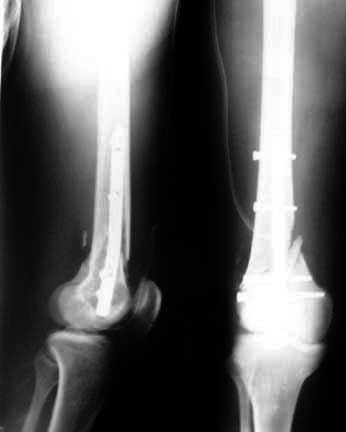

I did a debridement and could get a satisfactory field for internal stabilisation. The options I had kept were Ex fix, antegrade nailing and retrograde nailing. Had to be prepared for an arterial exploration if required. The vascular bundle was lying exposed through the compounding wound and could get the pulse beyond the fracture site. For this purpose I used a radioluscent flat table and did not use traction table intra-op.

After debridement I did a retrograde nailing using a solid SIGN nail. I thought this gave me the best chance to do with minimal disturbance to the head end on a flat table where the patient was supine. Sepsis to the knee was a worry but since I was using a solid nail I was fairly confident that the two area of concern( the fracture site and knee joint) will be sparated and will not spread infection from one place to other.

You will find attached in the remaining pictures the story of a young adult involved in a road traffic accident referred to us in shock. He had a major abdominal injury and had almost arrested before we took him up for surgery. After the abdomen was done I could boldly do the extremities thanks to the availability of nailing instruments and ventilator in the ICU. Of course he went through a rough period of rhabdomyolysis and an intensive critical care with daily battery of investigations which included electrolyte assessment, haemogram, blood gases, renal parmeters etc. Well yesterday I could shift him out of the ICU. Was his life and limbs saved through luxury of Western technology ?? I think it is only the availability of modern technology which has made us save these patients. Of course I envy the operation theatre I see in the Animal planet Channel. But with the limited infrastructure and not so high tech ICUs we can still save limbs and lives.